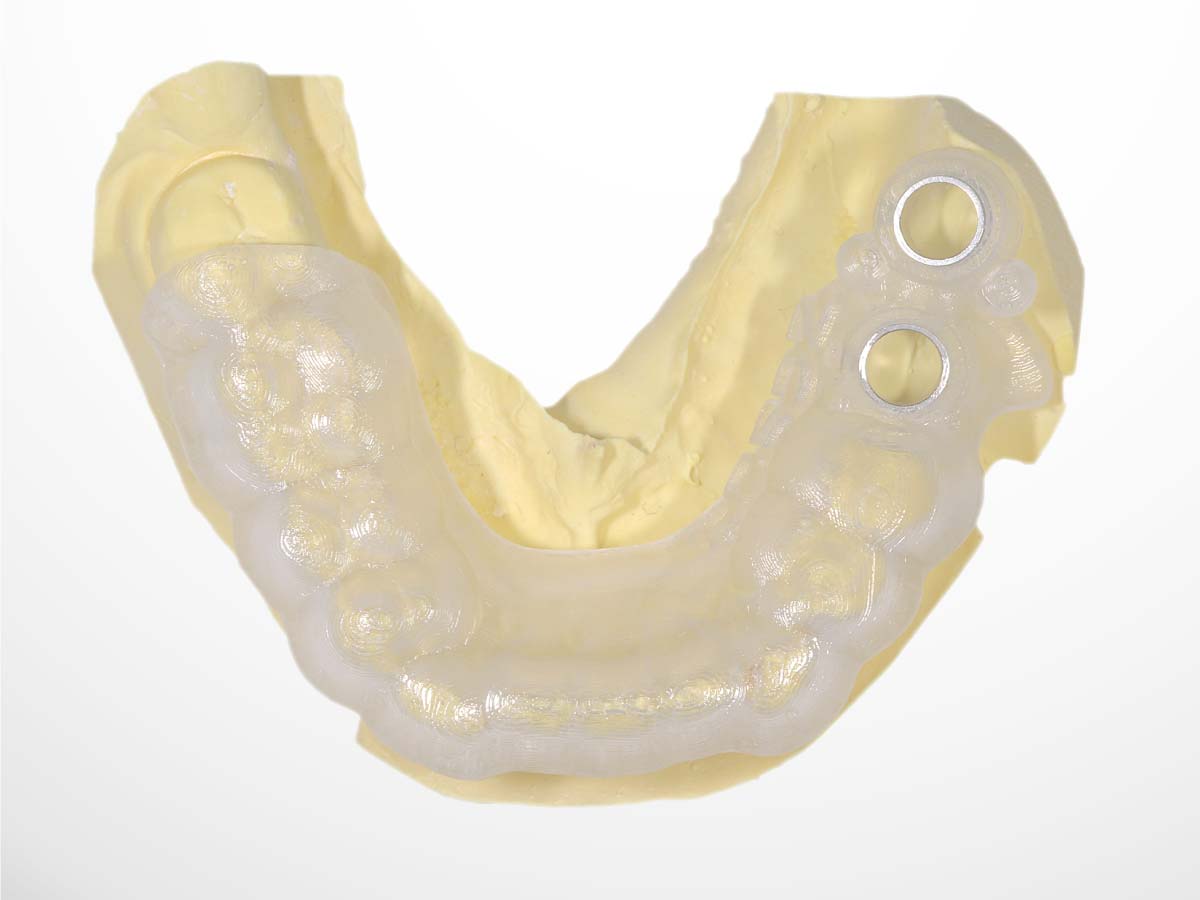

インプラントは埋入精度が仕上がりを大きく左右します。当院ではその精度をより高めるためにサージカルガイドを製作します。

サージカルガイドを作ることで、骨に穴を開けるドリルと、インプラントを入れる位置・角度・深さを高精度にすることができます。さらに手術時間を短くすることができるため、患者さんの身体の負担も軽減することができます。